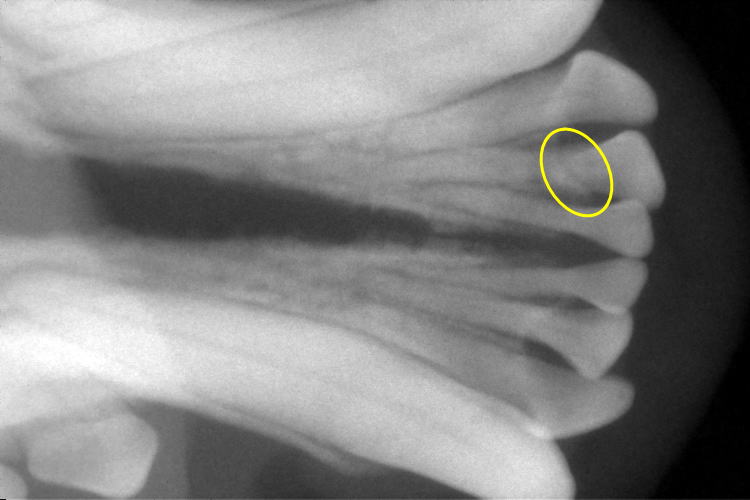

歯科レントゲン

下顎切歯部分です。

右下顎第2切歯が歯根破折していました。(黄色〇部分)